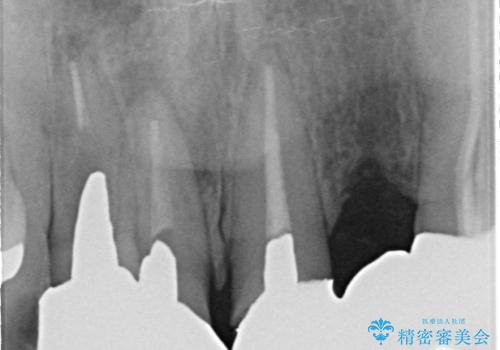

- 昔入れた被せ物と歯茎の間の隙間が気になると来院された方の症例です。

右上1、2番目の歯と左上1、2、3、番目の歯のブリッジを除去し、オールセラミッククラウンによる補綴を行うことで見た目を改善しました。

根管治療の注意事項(リスク・副作用など)

- 根管治療により類似の全ての症例の問題が解決するわけではなく、症例はあくまでも一例です

- 根管治療により痛みや腫れがひかない事や、術後に痛みや腫れが生じる事、治療によるファイル破折やパーフォレーションなどの偶発症、術後の歯根破折を生じる可能性もあります